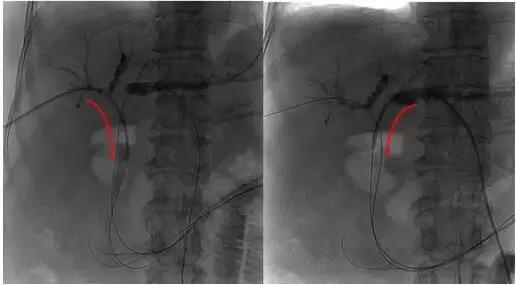

术中DSA下示意图:

1、 肿瘤病变狭窄段

2、插入射频消融导管

3、射频消融治疗及支架置入后造影再通